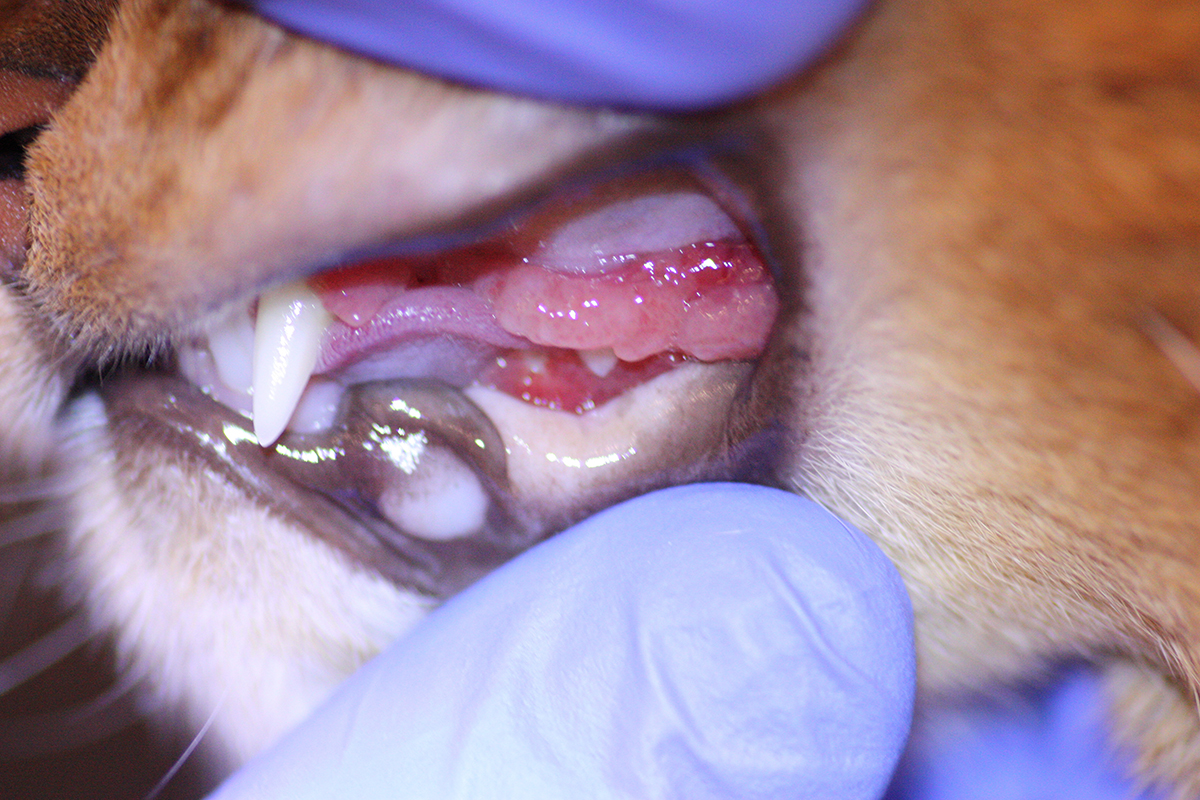

Абессин, 4,5 лет, лимфоцитарно-плазмоцитарный гингивостоматит левая сторона

Симптоматика чаще встречается у кошек, чем собак. Десны красные, изъязвление и часто легко кровоточат. Задняя часть рта, язык и губы складки могут быть затронуты аналогичными изъязвлениями. Кошки часто перестают есть, так как из-за множественных воспалительных процессах в тканях ротовой полости (полиинфломации), процесс потребления пищи становиться очень болезненным. У кошек отмечается плохое состояние шерсти, шерсть тусклая, взъерошенная, зачастую сальная. Кошки апатичны, вялые и не активные. У кошки обильно и часто выделяется слюна и ощущается неприятный запах изо рта.